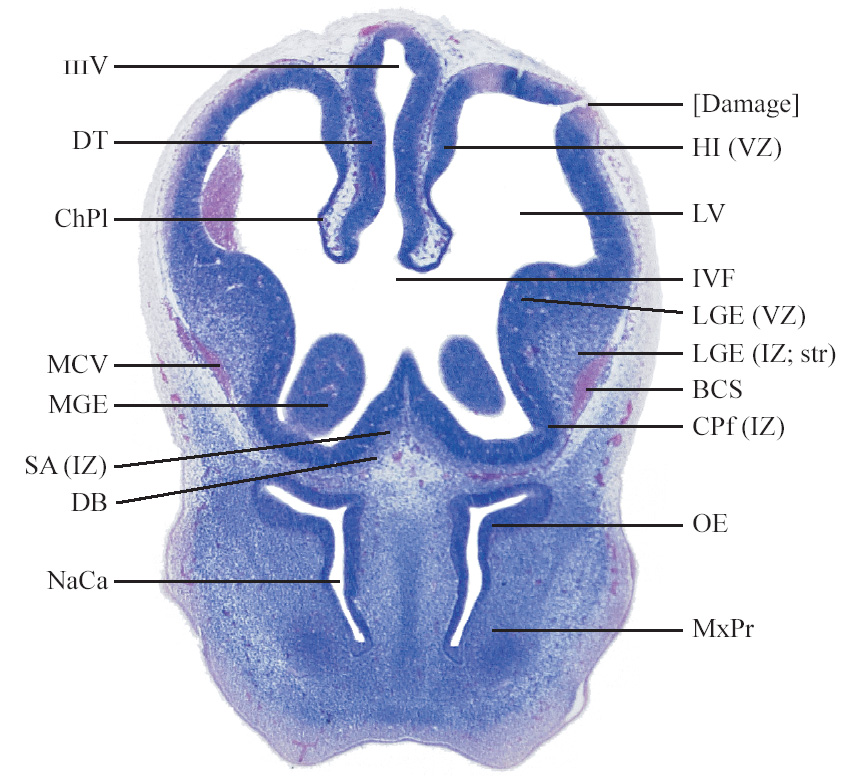

C57BL/6J GD12 Mouse Brain Atlas

Slides from U. Schambra, coronal cuts with slides at every 5th section, with a hematoxylin and eosin (H & E) stain

Currently on section 65.